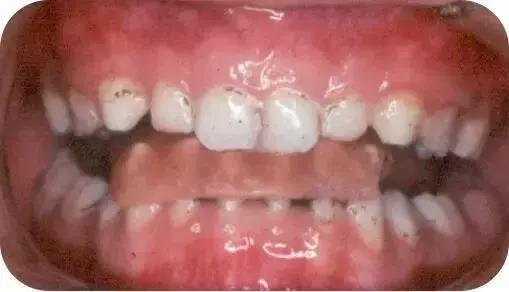

成人矫正案例一

成人矫正案例二